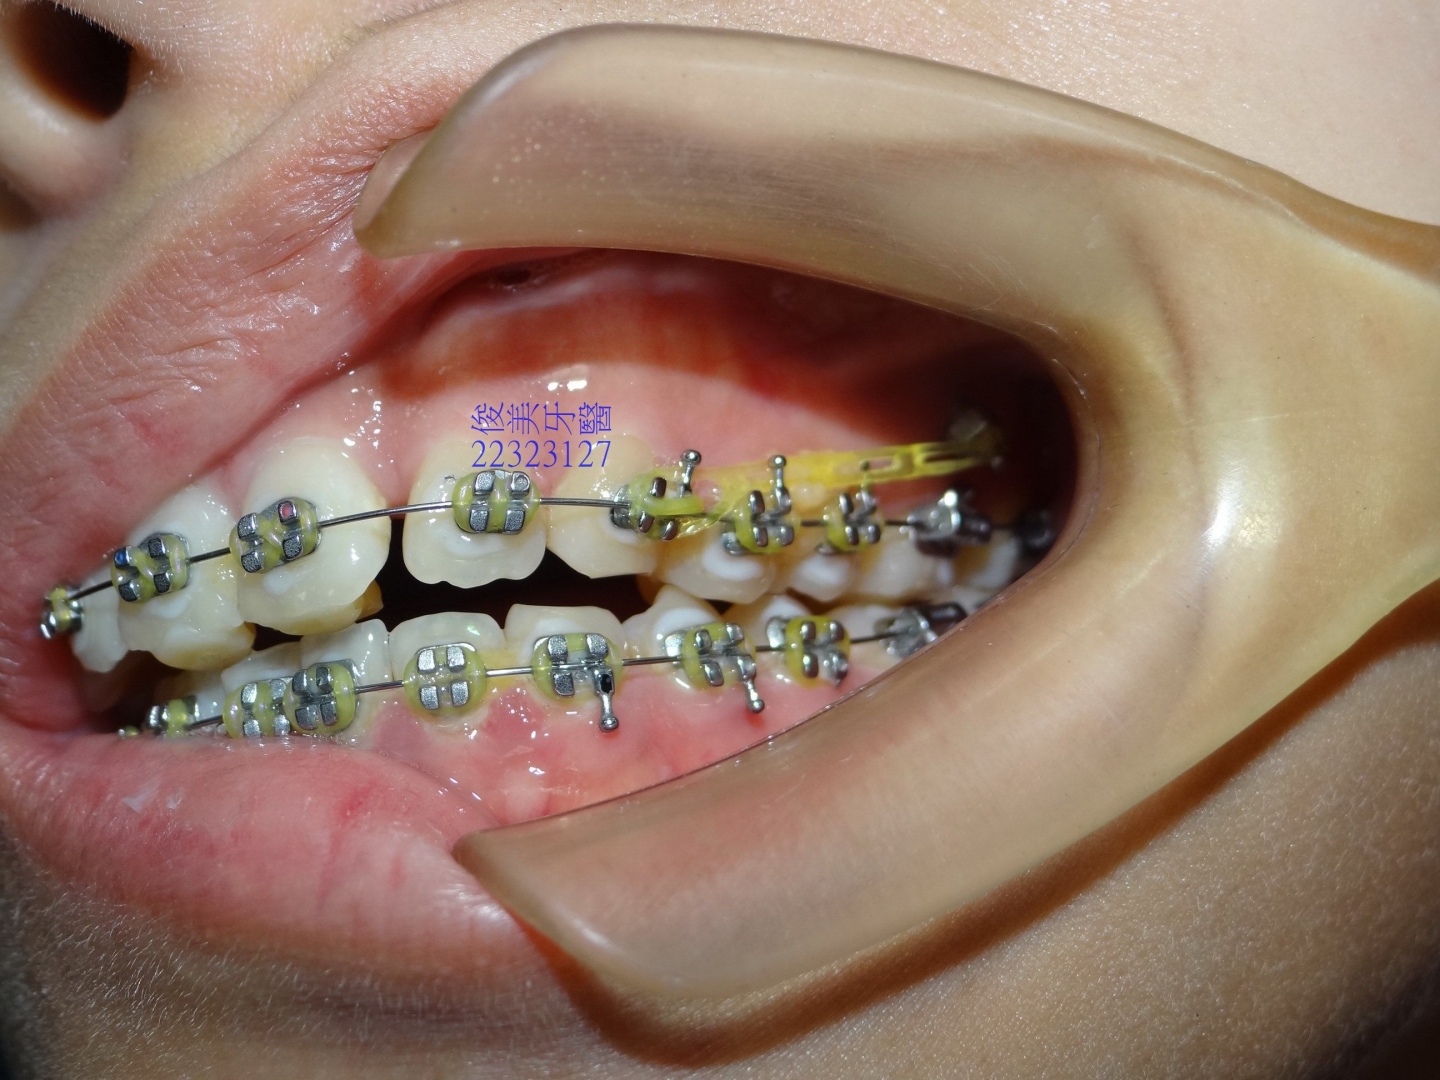

![]() 患者於門診中表示,牙齒很擁擠,想要改善;經醫師門診後,建議患者進行矯正治療即可改善。 ![]() 牙齒重疊... ![]() 有深咬現象... ![]() 上顎狀況... ![]() 下顎狀況... ![]() 左側咬合,牙齒往舌側傾斜...... . ![]() 右側咬合,牙齒往舌側傾斜...... ![]() 治療中....擁擠和深咬已改善.... ![]() 牙齒往後移.....將牙齒齒軸回正一點。 ![]() 治療結束,拆除矯正器了............. ![]() 患者好開心......牙齒整齊後,笑容更可愛了。 ![]() 也沒有暴牙的狀況。 ![]() 上顎牙弓狀況。 ![]() 下顎牙弓狀況。 ![]() 右側咬合狀況。 ![]() 左側咬合狀況。 ![]() 已拆除超過5年,依舊配戴維持器,保持最佳狀態。 |